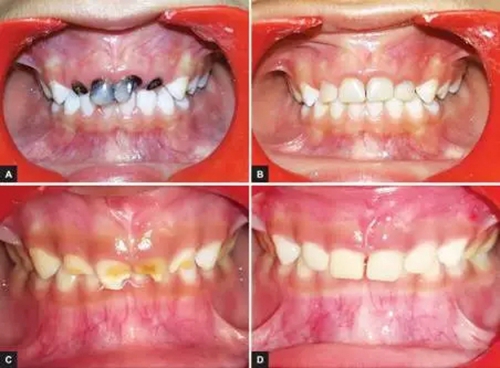

本研究中,其他患齲齒或牙外傷的患兒均采用此方法使用臨時冠材料進行美學(xué)修復(fù),下圖分別為兩例乳前牙齲齒(圖2)和兩例牙外傷(圖3)的病例。

圖2.(2-A,2-B為乳前牙齲齒病例1 2-C,2-D為乳前牙齲齒病例2)